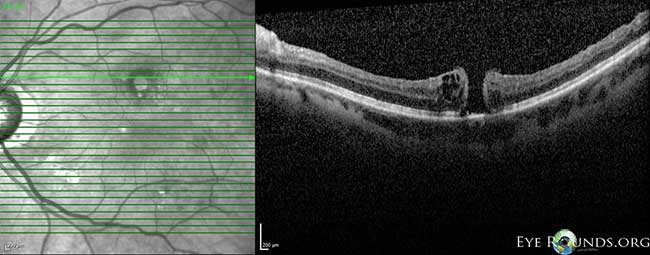

Fig 3-8: OCT OS: scant ERM remnants nasal to the fovea; thinning temporal in areas of prior membrane peeling.